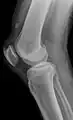

Quadriceps tendon rupture in plain X-ray